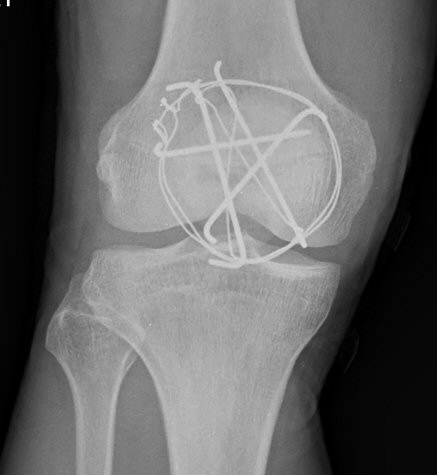

´Ü¼ø¹æ»ç¼±°Ë»ç

½½°³°ñ °ñÀý °íÁ¤ ÀåÄ¡°¡ °üÂûµÊ(»çÁø 6, 7)